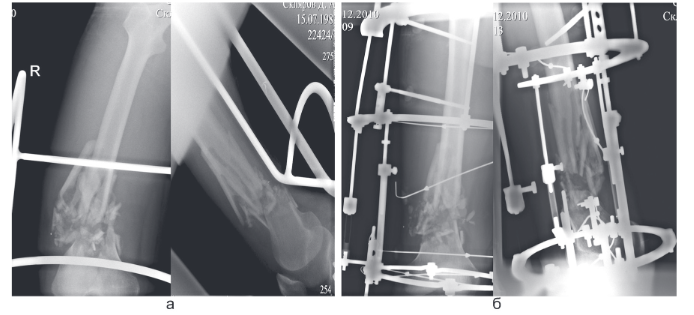

Техника остеосинтеза

Техника остеосинтеза 102 фотографий